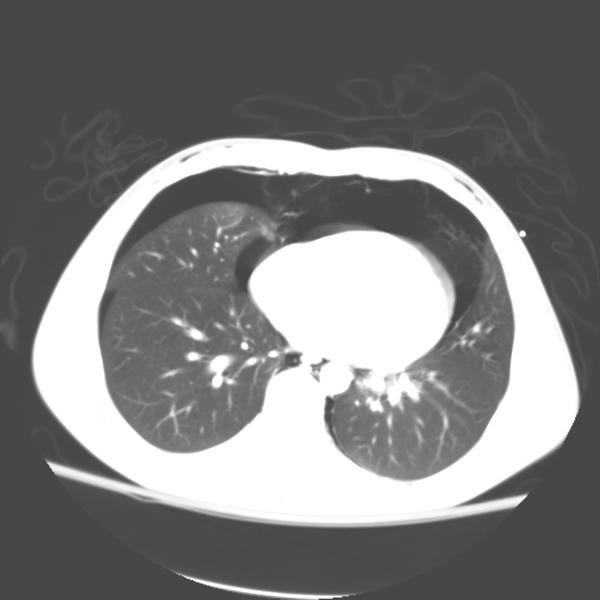

The patient is a 16-year-old male who was a restrained passenger in a car that collided with a guardrail at high speed. He was initially admitted to the referring hospital with no respiratory symptoms and with oxygen saturations over 90%. CT scan revealed a posterior membranous tracheal tear approximately 4 cm above the tracheal bifurcation, pneumomediastinum, and bilateral pneumothoraces. Upon arrival to our Level One Trauma Center, the patient was found to be hemodynamically stable, breathing spontaneously with oxygen saturations of 100% on 2L nasal cannula. His exam was remarkable for subcutaneous emphysema extending from his upper chest to his head, neck and throat. He had a seatbelt bruise across the front of his chest (Figure 1). The remainder of his exam was significant only for a left ankle injury. Review of his CT scan showed extensive mediastinal and subcutaneous emphysema, bilateral pneumothoraces and a posterior linear membranous tracheal tear starting from 2.5cm below the thoracic inlet and extending down 5cm above the carina (Figures 2a and b). Bronchoscopic intubation was performed confirming the CT scan findings and revealing no evidence of distal airway injury. The endotracheal tube was advanced across the area of injury under direct visualization.